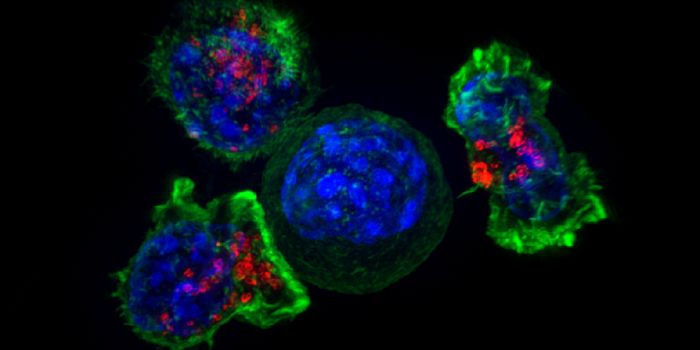

NOV 29, 2023CancerThe CAR-T Revolution: Developing T Cells into Cancer Assassins Cancer has long been a formidable foe, but recent ...

NOV 13, 2017ImmunologyThe battle between the immune system and growing tumors involves natural killer (NK) cells and a protective barrier put ...